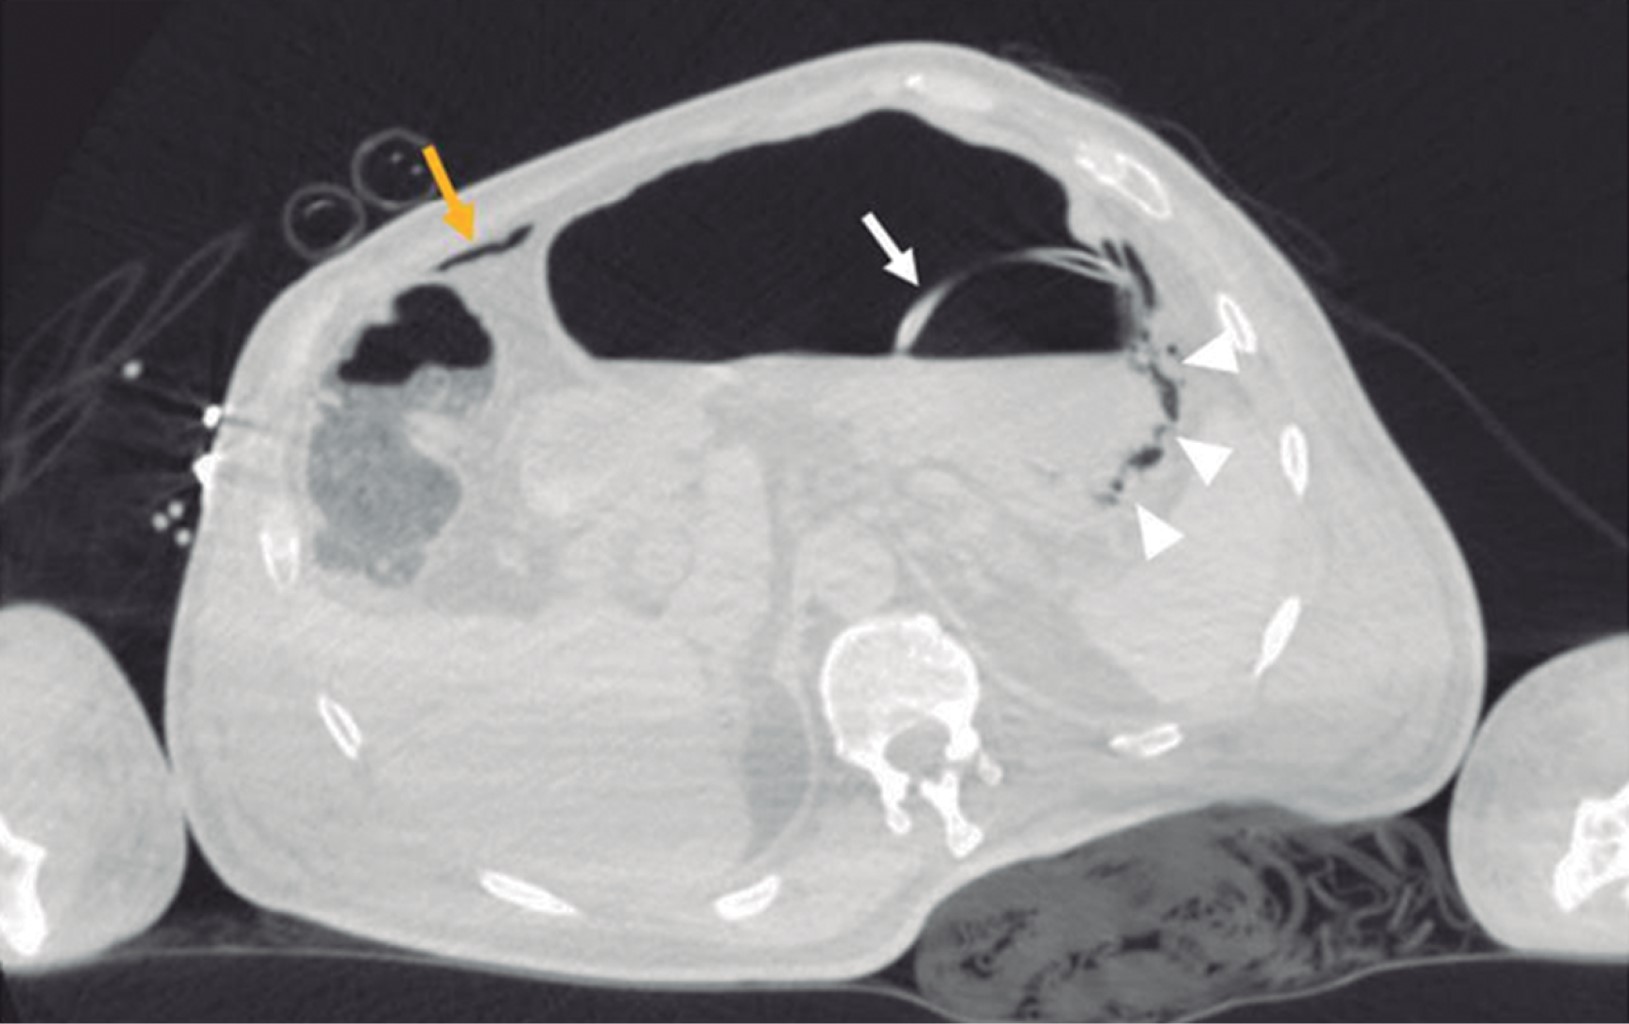

A 69-year-old male patient with a history of type 2 diabetes mellitus was treated with metformin and chlorpropamide. He also had hypertension treated with losartan and amlodipine. He presented to the emergency department with headache, chest pain, cough, myalgias, arthralgias, and dyspnea of one-week evolution. On admission, his heart rate was 114 bpm, respiratory rate 24 rpm, oxygen saturation 80% without supplemental oxygen support; his glucose was 587 mg/dl, white blood cells 25,690 cells/mm3, neutrophils 85%, lymphocytes 1.2%, hemoglobin 16.3 g/dl, procalcitonin 3.78 ng/dl, arterial blood gas with a pH of 7.41, pCO2 21 mmHg, PO2 35 mmHg, HCO3 13 mmol/l, oxygen saturation 62%. A rapid antigen test for SARS-CoV-2 was performed, and the result was positive; a CT scan of the chest showed radiological data suggestive of SARS-CoV-2 infection (Figure 1), and management with supplemental oxygen, insulin infusion pump, carbapenem antibiotics, antihypertensives, dexamethasone, and antithrombotic prophylaxis with enoxaparin was started. 48 hours after admission, the patient continued with septic shock, so vasopressor amines were started; an orotracheal intubation was performed and support with invasive mechanical ventilation was initiated. A nasogastric tube (NGT) was placed. After 24 hours of its placement, he presented hematemesis accompanied by abdominal distension, leukocytosis of 40,000 cells/mm3. A simple abdominopelvic CAT scan was performed, which revealed gastric pneumatosis and pneumoperitoneum (Figure 2). An urgent exploratory laparotomy was performed finding necrosis of the greater curvature of the stomach. A vertical gastrectomy was performed with GIA stapler with purple cartridges of 45 and 60 mm (Figure 3); the stapling line was reinforced with continuous a Prolene suture 00; a feeding jejunostomy tube was placed at 60 cm from the Treitz angle and Saratoga drains were left in place. Twenty-four hours later, the patient had hemodynamic stability, vasopressor amines were suspended, and enteral nutrition with an elemental diet was started. On the fifth postoperative day, the patient showed adequate tolerance to the enteral diet through jejunostomy. The methylene blue test was performed through the nasogastric tube showing no evidence of leaks; the white blood cell count decreased to 24,000 cells/mm3. Histopathology results were obtained revealing pan mural necrosis associated with arterial thrombosis secondary to microorganisms compatible with Mucor sp.; therefore, management with amphotericin B was initiated (Figures 4 and 5). During follow-up he showed good evolution; an abdominopelvic CT scan with contrast by the nasogastric tube was performed, which ruled out leaks and intra-abdominal collections and corroborated the integrity of the gastric wall; drains were removed, and the patient was discharged from general surgery on day 9 post-surgery, continuing to be managed by the internal medicine service. During the following days of hospitalization, the patient presented cardiovascular and pulmonary deterioration; a urine culture was taken, which showed growing of Candida tropicalis, and a CAT scan of the skull, thorax, and abdominopelvic with oral contrast was performed (Figures 6 and 7), The patient continued without evidence of abdominal leaks, rhino-cerebral and pulmonary mucormycosis were ruled out. A probable superimposed bacterial pneumonia and interstitial pneumopathy secondary to COVID-19 were reported. He showed persistent clinical deterioration and refractory shock and 29 days after admission.

On admission, the patient did not report any abdominal symptoms, so gastrointestinal involvement was not suspected. Subsequently, intravenous sedation and orotracheal intubation were performed, making it impossible for the patient to manifest gastric involvement. The only sign the patient presented was hematemesis 24 hours after the nasogastric tube placement, which ruled out the possibility of healthcare-associated mucormycosis since 24 hours are not enough to achieve the introduction, inoculation, and growing of the fungus. This led to the hypothesis that the patient acquired the fungal infection in his community. The diagnosis may be suspected by endoscopic findings, such as a fungal mass or necrotic lesions covering ulcerated areas that may perforate tissues and cause peritonitis.2 Often, the study protocol is initiated in the presence of an intra-abdominal abscess; the diagnosis can be made by biopsy of the suspicious area during surgery or endoscopy.7 Few samples are usually sent for culture,2 and those sent are positive in only 30%, in addition, specialized culture media such as potato dextrose agar are required for fungal growing.12 Confirmatory molecular tests that may detect surface antigens are also required, but they are not yet available.2 CT findings may include focal or diffuse thickening of the gastric wall, pneumatosis with decreased wall enhancement on contrast administration (emphysematous gastritis) secondary to ischemia and necrosis, adjacent collections, wall necrosis with focal disruption or perforation, and rarely, pneumoperitoneum.13 When hematemesis occurs, the next diagnostic step should be an upper endoscopy. However, the abdominal distention presented by the patient suggested a high probability of perforation of the hollow viscera, so initially, a CT scan of the abdomen was performed. A surgical emergency was considered when reporting gastric pneumatosis and pneumoperitoneum, ruling out an endoscopy. Exploratory laparotomy allows direct exploration of the stomach and partial resection of the stomach as a diagnostic and therapeutic measure. Treatment consists of antifungal and urgent surgical debridement since necrotic tissue's presence will affect the antifungal's penetration to the tissues; additionally, aggressive medical support for comorbidities should be provided.14 Intravenous liposomal amphotericin B is the treatment of choice. It is more effective than conventional amphotericin B.15 Delaying the initiation of amphotericin for more than six days, doubles mortality.4 Although most of literature favors aggressive surgical treatment, we opted for a more conservative treatment by preserving a portion of the stomach and performing only a vertical gastrectomy since macroscopic inspection showed a clear demarcation between necrotic and viable tissues. We consider that the surgical treatment we performed was correct since, in the post-surgical follow-up, the patient had a good evolution; the methylene-blue test and the two abdominal CT scans with contrast in the stomach through the nasogastric tube allowed us to verify the integrity of the suture line from the first post-surgical day until the day of his death. The sample sent to pathology allowed to make the diagnosis and thus initiate targeted therapy with amphotericin B, and since no fungal infection by Mucor sp. at any other organic level was found, the cause of death was attributed to nosocomial infectious complications at the pulmonary and urinary level.

Figure 3